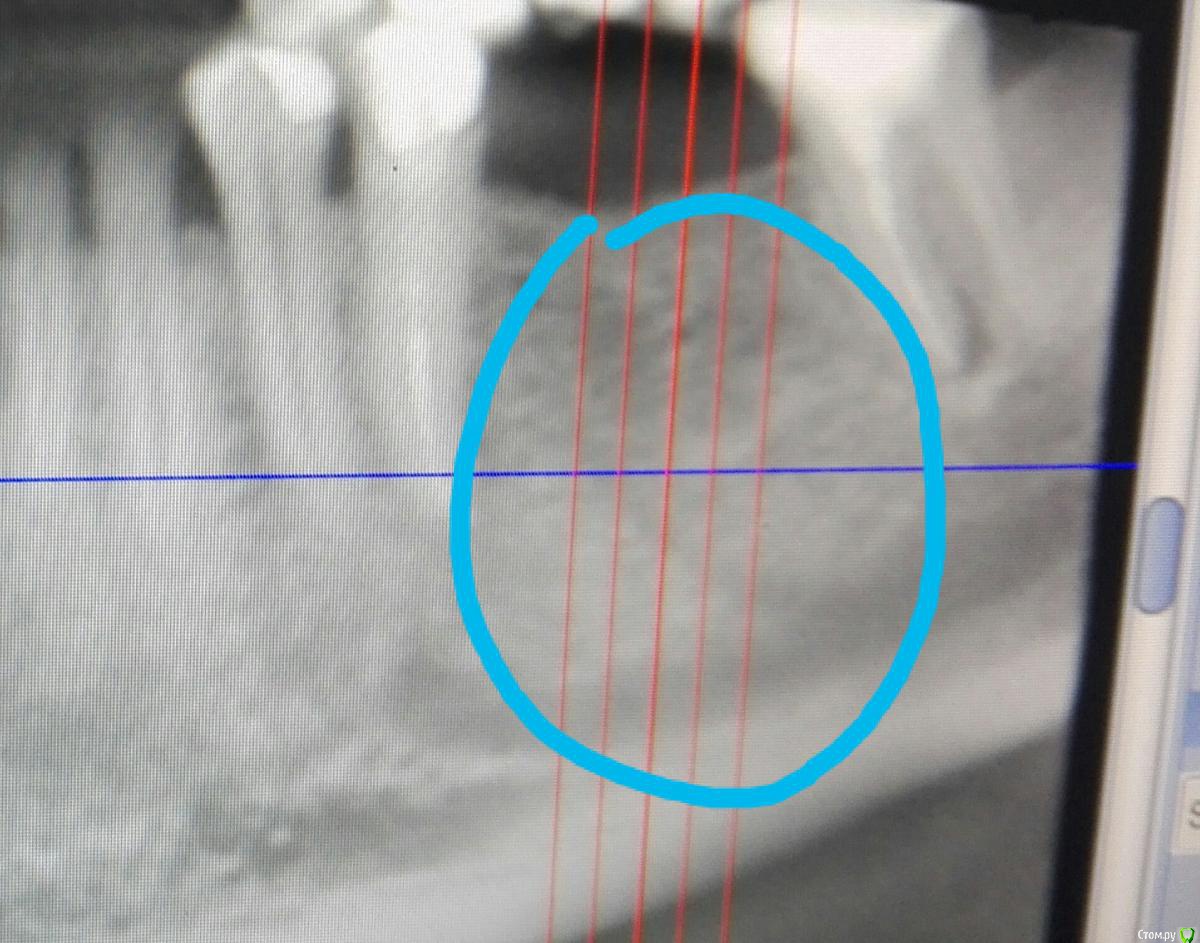

Aldo Rain Опубликовано 5 февраля, 2011 Поделиться Опубликовано 5 февраля, 2011 Будет возможность покажите срез с КТ Ссылка на комментарий

Bier Опубликовано 6 февраля, 2011 Автор Поделиться Опубликовано 6 февраля, 2011 ок постараюсь, как раз на работе такая КТшка лежит... Ссылка на комментарий

karasov Опубликовано 20 октября, 2016 Поделиться Опубликовано 20 октября, 2016 (изменено) В области 36 работал с ламиной. Наткнулся на нерв. Причем два. Один обошел , второй нет. Что ждать?на кт ееееле заметны Изменено 20 октября, 2016 пользователем karasov Ссылка на комментарий

karasov Опубликовано 21 октября, 2016 Поделиться Опубликовано 21 октября, 2016 не похож на нерв. имхо.По кт есть однозначно связь с нижним альвеолярным. Визуально на сосуд не похоже Ссылка на комментарий

karasov Опубликовано 21 октября, 2016 Поделиться Опубликовано 21 октября, 2016 Слева был, справа есть Ссылка на комментарий